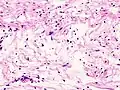

| Micrograph of a schwannoma showing both a cellular Antoni A area (top) and a loose paucicellular Antoni B area (bottom). HE stain. | |

A schwannoma (or neurilemmoma) is a usually benign nerve sheath tumor comprising Schwann cells, which normally produce the insulating myelin sheath covering peripheral nerves.

Schwannomas are homogeneous tumors, consisting only of Schwann cells. The tumor cells always stay on the outside of the nerve, but the tumor itself may either push the nerve aside and/or up against a bony structure (thereby possibly causing damage). Schwannomas are relatively slow-growing. For reasons not yet understood, schwannomas are mostly benign and less than 1% become malignant, degenerating into a form of cancer known as neurofibrosarcoma. These masses are generally contained within a capsule, so surgical removal is often successful.[3]

Verocay bodies are seen histologically in schwannomas.